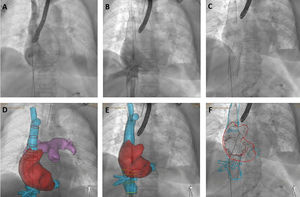

La cirugía de la insuficiencia tricuspídea grave aislada es poco frecuente. Entre las alternativas percutáneas, está el implante de prótesis valvulares heterotópicas en ambas venas cavas (CAVI). El sistema valvular puede ir montado sobre un stent recubierto entre ambas cavas (Tricentro, NVT, Suiza) o sobre prótesis independientes (TricValve, Products&Features, Alemania). La selección de los pacientes y los tamaños de prótesis se basa en la tomografía computarizada (TC). El procedimiento se realiza habitualmente con angiografías selectivas, emplazando un catéter en la rama pulmonar derecha y un catéter o guía en la transición hacia la vena cava inferior (figura 1A,B).

Nuestro grupo ha explorado el papel de la fusión TC-fluoroscopia (HeartNavigator 3.0, Philips, Países Bajos) en 6 pacientes consecutivos (Tricentro 2, TricValve 4), con colocación de marcadores específicos (Tricentro: desembocadura de las cavas y orientación de la neoválvula; figura 2A,B; TricValve: mismas medidas y alturas que el cribado; figura 1D,E). En nuestra experiencia, fue un complemento preciso: mejoró la comprensión anatómica, permitió posicionar el arco de fluoroscopia ortogonal a la zona objetivo, retirar el catéter pig-tail antes del despliegue, con lo que se evita enjaularlo y se mantienen las referencias o se detecta un inadvertido mal posicionamiento del catéter en la rama pulmonar (delimita los bordes y el volumen de la arteria, mientras que el catéter puede posicionarse en aspecto superior o inferior y puede disminuir la precisión del implante). También podría reducir las angiografías selectivas y el material de referencia utilizado, aunque esto no fue objeto de análisis en nuestra experiencia inicial. El resultado final comparado se observa en la figura 1C,F y la figura 2C,D.